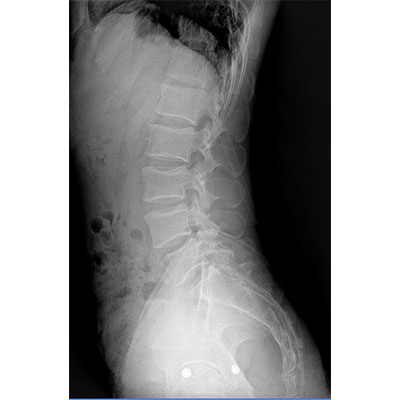

● 采用自主研發(fā)的技術,在保證優(yōu)質圖像的前提下,大大降低X射線劑量,用心呵護醫(yī)護工作者及患者的健康。

● 短曝光時間,便于老年人、兒童、殘疾人進行臨床拍攝。避免這類群體因不能有效控制身體運動等因素造成的運動偽影,提高攝片質量及效率。